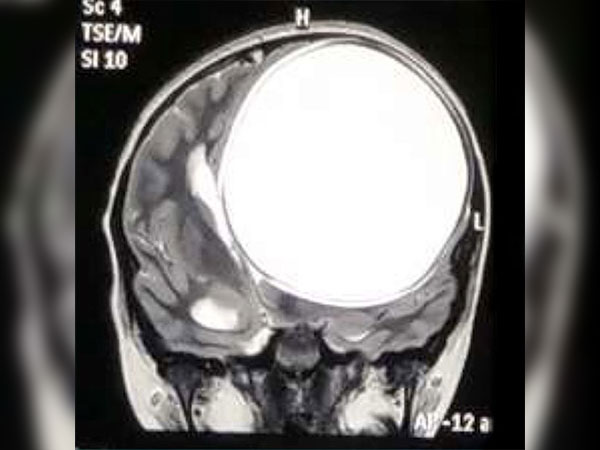

ನರರೋಗ ತಜ್ಞರು ಆಕೆಯನ್ನು ಪರೀಕ್ಷಿಸಿ ಎಂಆರ್ ಐ ಸ್ಕ್ಯಾನ್ ಮಾಡಿದ ಬಳಿಕ ಬಾಲಕಿಯ ತಲೆಯಲ್ಲಿ ಟೇಪ್ ವರ್ಮ್ ಕೋಶ ಇರುವುದು ಪತ್ತೆಯಾಗಿದೆ ಮತ್ತು ಇದು ಮೆದುಳಿನ ಅರ್ಧ ಭಾಗದಷ್ಟಿತ್ತು.

ನೀತಾಳ ತಲೆಯಲ್ಲಿ ಪತ್ತೆಯಾದ ಕೋಶ ಸುಮಾರು 675 ಗ್ರಾಂನಷ್ಟು ಭಾರವಿತ್ತು ಮತ್ತು 12.2 ಸೆ.ಮೀx11ಸೆ.ಮೀ.x9.8 ಸೆ.ಮೀ. ನಷ್ಟಿತ್ತು.

ಕೋಶ ಸಾಮಾನ್ಯಕ್ಕಿಂತ ತುಂಬಾ ದೊಡ್ಡದಾಗಿ ಬೆಳೆದಿತ್ತು ಮತ್ತು ಇದು ತಲೆಯನ್ನು ಸಿಡಿಯುವ ಸಾಧ್ಯತೆ ಕೂಡ ಇತ್ತು. ಈ ವೇಳೆ ಬಾಲಕಿ ಸಾವನ್ನಪ್ಪುತ್ತಿದ್ದಳು. ಬಾಲಕಿ ಸರಿಯಾದ ಸಮಯದಲ್ಲಿ ಪರೀಕ್ಷೆಗೆ ಒಳಪಟ್ಟಳು. ಶಸ್ತ್ರಚಿಕಿತ್ಸೆಯ ಮೂಲಕ ನರರೋಗ ತಜ್ಞರು ಬಾಲಕಿಯನ್ನು ಅಪಾಯದಿಂದ ಪಾರು ಮಾಡಿದ್ದಾರೆ. ನೀತಾ ಪರಿಸ್ಥಿತಿ ಈಗ ಸುಧಾರಣೆಯಾಗಿದೆ ಮತ್ತು ಆಕೆ ಚೇತರಿಸಿಕೊಳ್ಳುತ್ತಿದ್ದಾಳೆ ಎಂದು ಕೇಳಲು ತುಂಬಾ ಖುಷಿಯಾಗುತ್ತಿದೆ. ಬಾಲಕಿಗೆ ಸಂತೋಷ ಹಾಗೂ ಅದೃಷ್ಟ ಸಿಗಲಿ ಎಂದು ಹಾರೈಸುತ್ತೇವೆ.